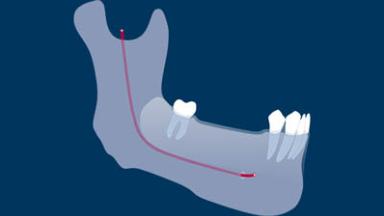

Once an implant is placed, there are three loading protocols that may be used. An implant loading protocol is defined as the time elapsed between implant placement and the attachment of the prosthesis so that the implant is brought into function.

Conventional loading of dental implants is defined as loading 2 or more months after implant placement. This is a well-established protocol that allows for complete healing of bone and peri-implant soft tissues prior to prosthesis attachment.

In an early loading protocol, the prosthesis is attached between 1 week and 2 months subsequent to implant placement. The implants are put into function during the later stages of bone healing but prior to complete healing of soft tissues. This results in a relatively reduced treatment time between implant placement and loading compared to the conventional loading protocol.

In contrast, immediate loading of dental implants is defined as prosthesis attachment within 1 week of implant placement, including the day of surgery. In this case, the process of peri-implant bone and soft tissue healing occurs with the provisional prosthesis attached to the implant from the outset.